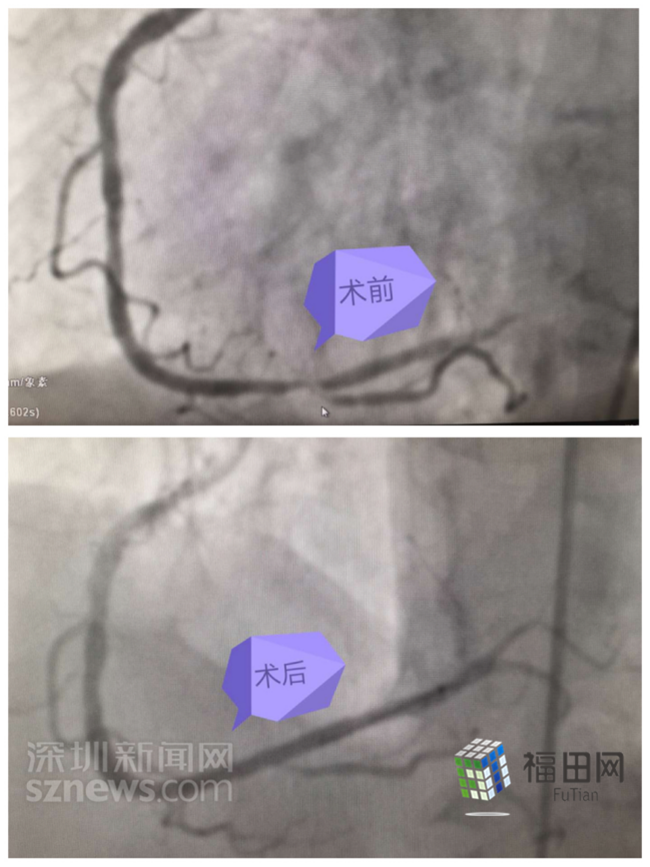

术前术后对比图。

经检查发现,供应杨奶奶心脏的右冠状动脉远段90%次全闭塞、后降支开口99%次全闭塞,前降支近段60%弥漫性狭窄,回旋支中段50%弥漫性狭窄;杨奶奶还有基础病,高血压10余年、心律失常(房颤)、糖尿病、慢性阻塞性肺气肿;86岁高龄......所有这一切不利因素,都未能阻挡中大八院一站式“救心”战役的脚步!

对于杨奶奶治疗的关键是争分夺秒的急诊行PCI术(经皮冠状动脉介入治疗),迅速恢复梗死血管的血流,最大程度的恢复冠状动脉的血供,防止心肌发生进一步的坏死。

紧急手术!胸痛中心医护团队迅速实施生命接力!张焕基副主任和房兴锐副主任医师,迅速开通闭塞血管,放入支架,胸痛中心吴剑胜主任也赶到现场指挥抢救!